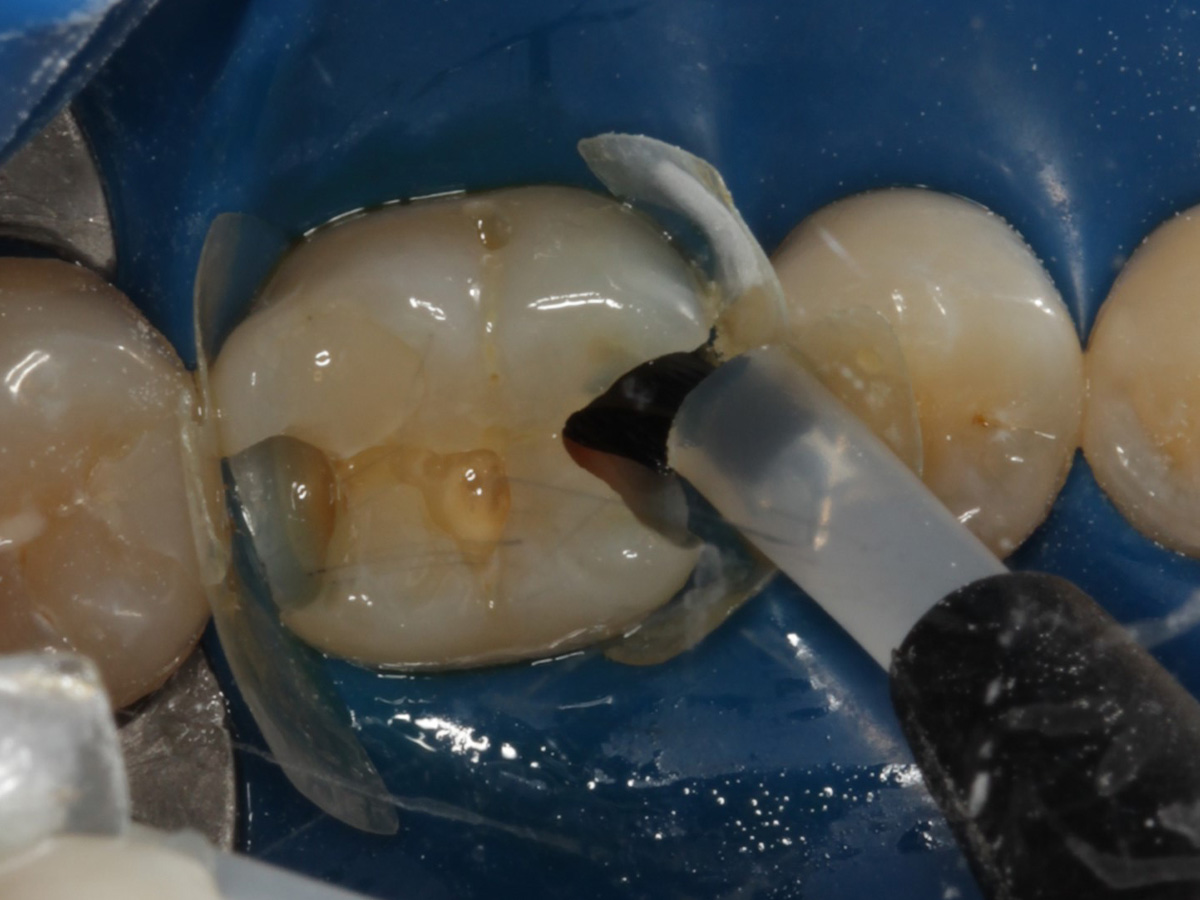

Abbildung 12

Applikation der Matrizen: Evolve Blau Molar 5 mm distal und 6 mm mesial

Abbildung 13

Schmelzätzung bei liegenden Matrizen

Abbildung 14

Abbildung 15

Nach Spray und Trocknung der Kavität